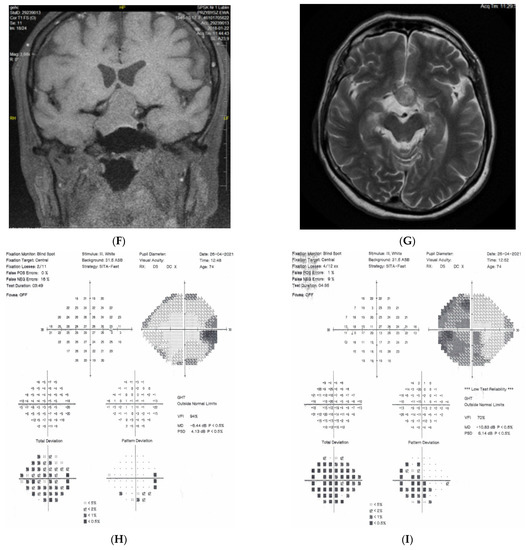

2.2. Case 2

2.3. Case 3